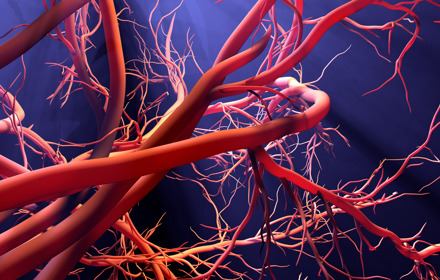

No benefit for half of people taking statins